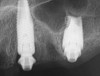

Fig 41. Postoperative periapical x-rays on the day of surgery demonstrating ideal immediate implant placement in bone.

Figure 41

Fig 42. Postoperative periapical x-rays on the day of surgery demonstrating ideal immediate implant placement in bone.

Figure 42

Postoperative x-rays documented the full seating of the prosthesis on the multi-unit abutments (Figure 21 and Figure 22). The patient returned at 1 week postoperatively for a follow-up visit and to review home care. She remarked that the restoration was comfortable and that she was free of discomfort and extremely pleased with the makeover she received in one day.